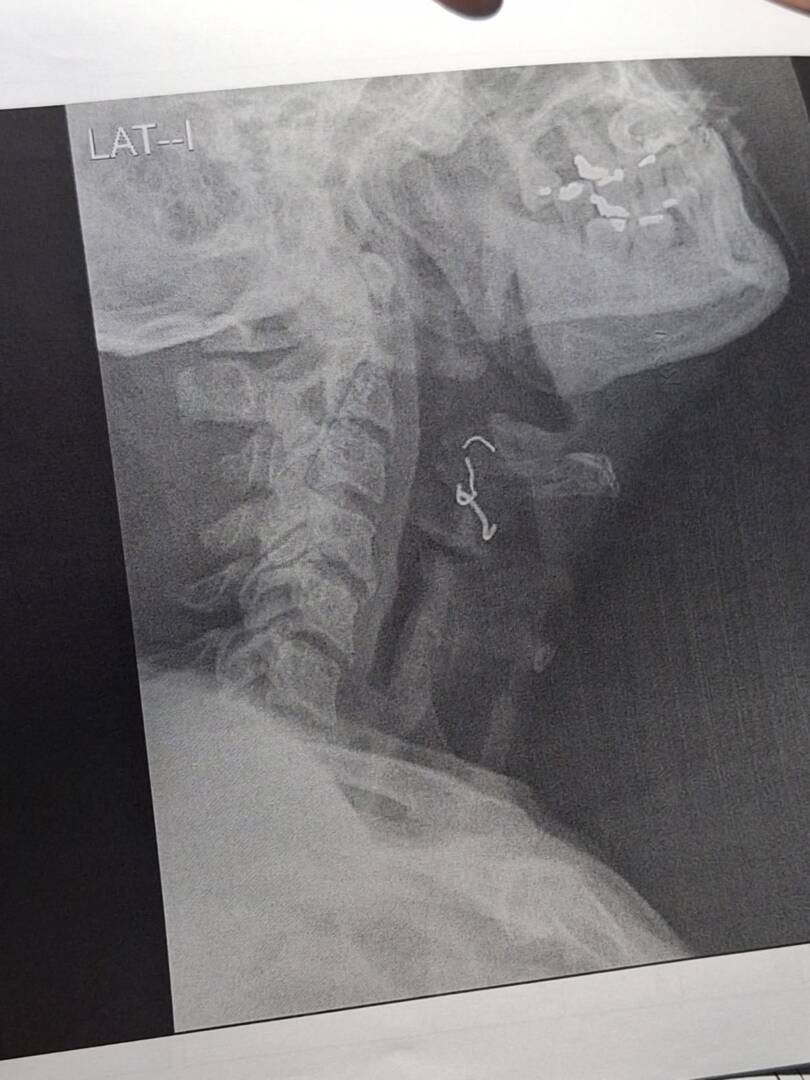

A pesar de que familiares comunicaron este incidente a los médicos, según sus familiares, ellos no tomaron en cuenta la advertencia. Rosario del Pilar Ramírez Fasabi, esposa del paciente, afirmó que alertó a los profesionales de la salud, pero estos consideraron la posibilidad como improbable. Fue sólo al solicitar una placa durante el proceso de alta que descubrieron la dentadura incrustada en la garganta de Cotrina Flores.

La situación se agrava, ya que el paciente requiere una intervención de emergencia en Lima debido a la delicadeza de su caso. Sin embargo, hasta el momento, no se ha agilizado la documentación necesaria. Son cuatro días que el paciente no puede ingerir sus alimentos, el estado de salud de Guillermo se deteriora rápidamente. La presencia del objeto en su garganta provoca la generación de mucosidad, que se introduce en su pulmón derecho, aumentando el riesgo de una posible neumonía.